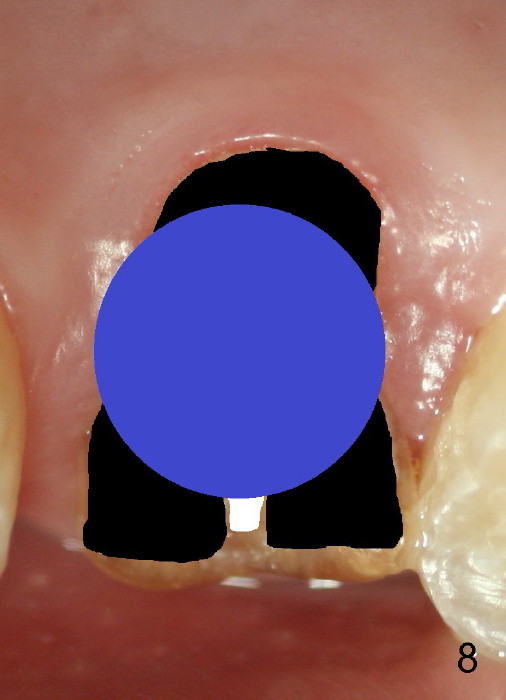

Fig.8 illustrates the implant (blue) placed in the middle of the socket. The remaining buccal and lingual gaps (black) are then closed by graft and membrane. Placing the graft in the deeper portion of the mesiobuccal socket is not so easy because the large implant blocks the entrance (Fig.7 between lower arrowheads). If more graft has been dispensed and the earlier PA shows larger upper space exists (Fig.6 between upper arrowheads), the graft should be placed to that region prior to implant placement.